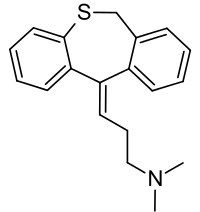

Chemistry

Dosulepin is a tricyclic compound, specifically a dibenzothiepine, and possesses three rings fused together with a side chain attached in its chemical structure.[23] It is the only TCA with a dibenzothiepine ring system to have been marketed.[23][24] The drug is a tertiary amine TCA, with its side chain-demethylated metabolite northiaden (desmethyldosulepin) being a secondary amine.[25][26] Other tertiary amine TCAs include amitriptyline, imipramine, clomipramine, doxepin, and trimipramine.[27][28] Dosulepin exhibits (E) and (Z) stereoisomerism like doxepin but in contrast the pure E or trans isomer is used medicinally.[1][10][29] The drug is used commercially as the hydrochloride salt; the free base is not used.